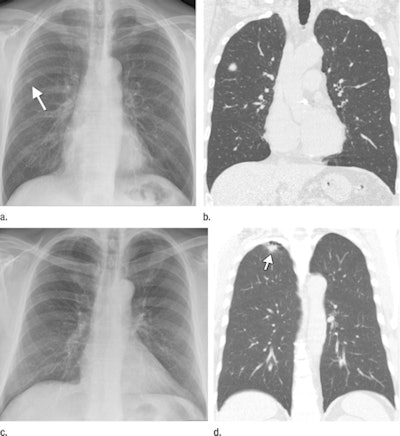

| (a) Digital radiography can localize lung cancers, such as an 11.4-mm diameter malignancy considered as definitely present in separate readings by three radiologists and a radiology resident. (b) Tumor's presence is confirmed with CT. (c, d) But lung malignancies can be undetectable with DR, even when their presence on CT had been previously disclosed to the observers. Images provided by Dr. Bartjan de Hoop; republished with permission of the Radiological Society of North America. |

Twenty-four (44%) malignancies were correctly localized by the four physicians. At level 5, for example, the sensitivity of DR for correctly localized malignant lesions ranged from 18% to 49% at a specificity of 100%. The false-positive rates in the control group ranged from 0% to 13%.

Seven (13%) metastatic lesions were missed by all observers, and three of the seven remained undetectable on the radiographs even when CT findings were known. Depending on reader experience, de Hoop and colleagues concluded that 22% to 63% of the lung cancers detected with CT would have been missed if chest DR had been used alone.